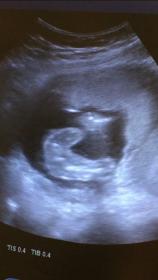

Self-made ultrasound at 16 weeks!

Hi, I am a pediatrician and did try to do an ultrasound on myself (with some watching colleagues) at 15+4 weeks for a potty shot of our third baby.

As we normally use the ultrasound differently I am not experienced with fetusses! Now we have three opinions- I thought the thing between the legs was the cord- one colleague said it SO looked like a penis with scrotum in the one pic (she has a point), two others said "not enough evidence" to decide ;-)

What do you think? We have no nub shot from our (expert) scan at 12+4, only this potty shot. Attachment 41406